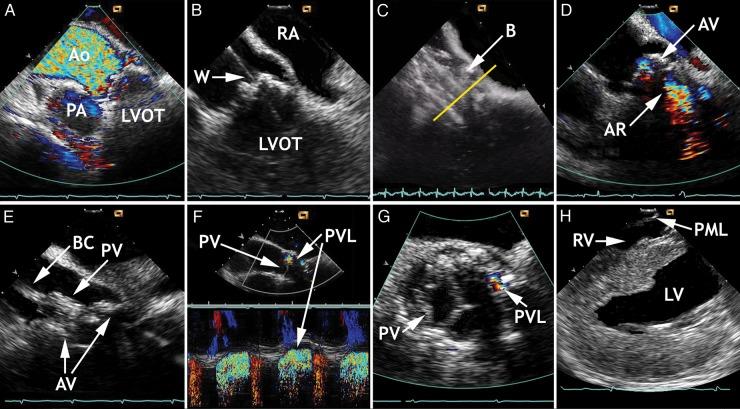

Current interventional procedures in structural heart disease and cardiac arrhythmias require peri-interventional echocardiographic monitoring and guidance to become as safe, expedient, and well-tolerated for patients as possible. Intracardiac echocardiography (ICE) complements and has in part replaced transoesophageal echocardiography (TEE), including real-time three-dimensional (RT-3D) imaging. The latter is still widely accepted as a method to prepare for and to guide interventional treatments. In contrast to TEE, ICE represents a purely intraprocedural guiding and imaging tool unsuitable for diagnostic purposes. Patients tolerate ICE much better, and the method does not require general anaesthesia. Accurate imaging of the particular pathology, its anatomic features, and spatial relation to the surrounding structures is critical for catheter and wire positioning, device deployment, evaluation of the result, and for ruling out complications. This review describes the peri-interventional role of ICE, outlines current limitations, and points out future implications. Two-dimensional ICE has become a suitable guiding tool for a variety of percutaneous treatments in patients who are conscious or under monitored anaesthesia care, whereas RT-3DICE is still undergoing clinical testing. Continuous TEE monitoring under general anaesthesia remains a widely accepted alternative.

目前,结构性心脏病和心律失常的介入治疗需要围介入期超声心动图监测和引导,以使患者尽可能安全、便捷且耐受性良好。心内超声心动图(ICE)补充并部分取代了经食管超声心动图(TEE),包括实时三维(RT-3D)成像。后者仍被广泛认可为一种用于准备和引导介入治疗的方法。与TEE不同,ICE是一种纯粹的术中引导和成像工具,不适合用于诊断目的。患者对ICE的耐受性要好得多,且该方法不需要全身麻醉。对特定病变及其解剖特征以及与周围结构的空间关系进行准确成像,对于导管和导丝定位、器械部署、结果评估以及排除并发症至关重要。本综述描述了ICE在围介入期的作用,概述了当前的局限性,并指出了未来的意义。二维ICE已成为清醒或接受麻醉监测的患者进行各种经皮治疗的合适引导工具,而实时三维心内超声心动图(RT-3DICE)仍在进行临床试验。全身麻醉下持续的TEE监测仍然是一种广泛接受的替代方法。